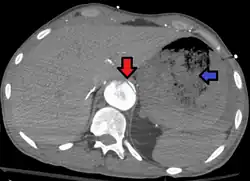

| Aorto enteric fistula and aortic dissection of the thoracic aorta. Arrow shows the flap in the aorta. Heterogeneity is blood in the stomach |

An aortoenteric fistula is a connection between the aorta and the intestines, stomach, or esophageus.[1] There can be significant blood loss into the intestines resulting in bloody stool and death.[1] It is usually secondary to an abdominal aortic aneurysm repair. The third or fourth portion of the duodenum is the most common site for aortoenteric fistulas, followed by the jejunum and ileum.[2]